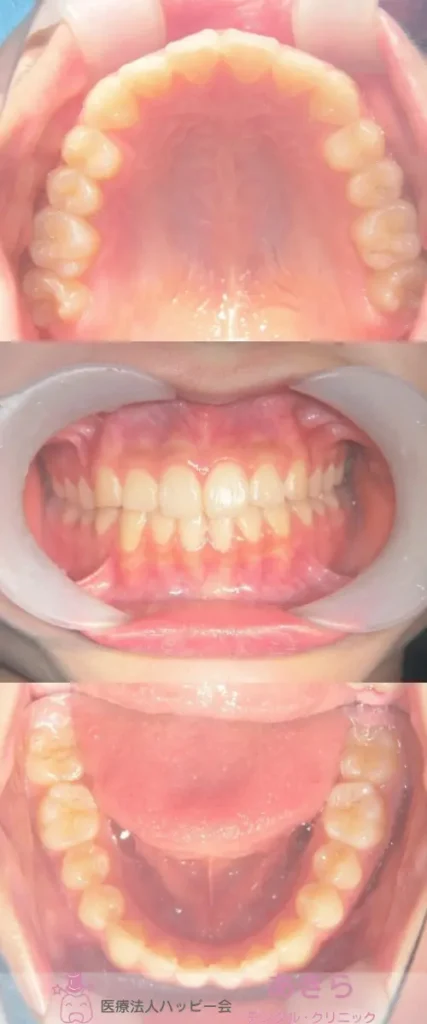

当院の症例

SH療法

SH療法-症例-No.015-上顎前突を伴なう歯幅が小さい症例

山形市の歯医者「あきらデンタル・クリニック」のSH療法の症例をご紹介します。 SH… -